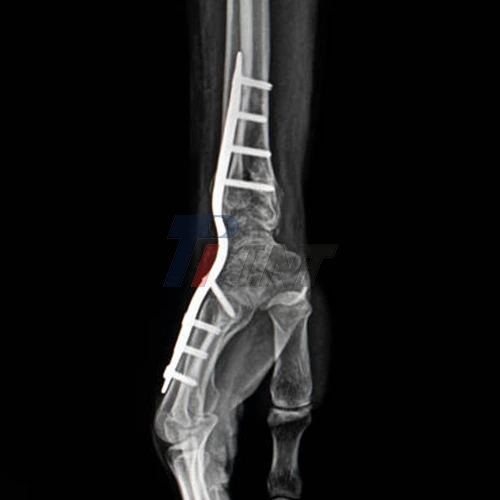

Wrist wounds can be weakening, regularly requiring surgical intercession to reestablish usefulness and lighten torment. One common arrangement in orthopedic surgery is the use of titanium plates to stabilize breaks or combine bones. Whereas titanium plate in wrist surgery has become a standard practice, numerous patients ponder potential complications or long-term impacts. This article delves into the world of titanium inserts, investigating their benefits, conceivable issues, and what you need to know if you're considering or have experienced this procedure.

Titanium plates play a pivotal part in wrist surgeries, especially in cases of complex breaks or arthrodesis (joint fusion). These plates are outlined to hold bone parts in place, permitting appropriate mending and arrangement. The utilization of titanium in restorative implants has revolutionized orthopedic surgery due to its unique properties:

During wrist surgery, orthopedic specialists carefully select the fitting titanium plate based on the particular harm and persistent life systems. These plates come in different shapes and sizes, permitting customized treatment approaches. The strategy regularly includes making an incision, realigning the bones, and securing the plate with screws. Whereas titanium plates offer various points of interest, it's basic to understand that any surgical intercession carries potential dangers and complications. Let's investigate a few of the issues that patients might experience after titanium plate addition in wrist surgery.